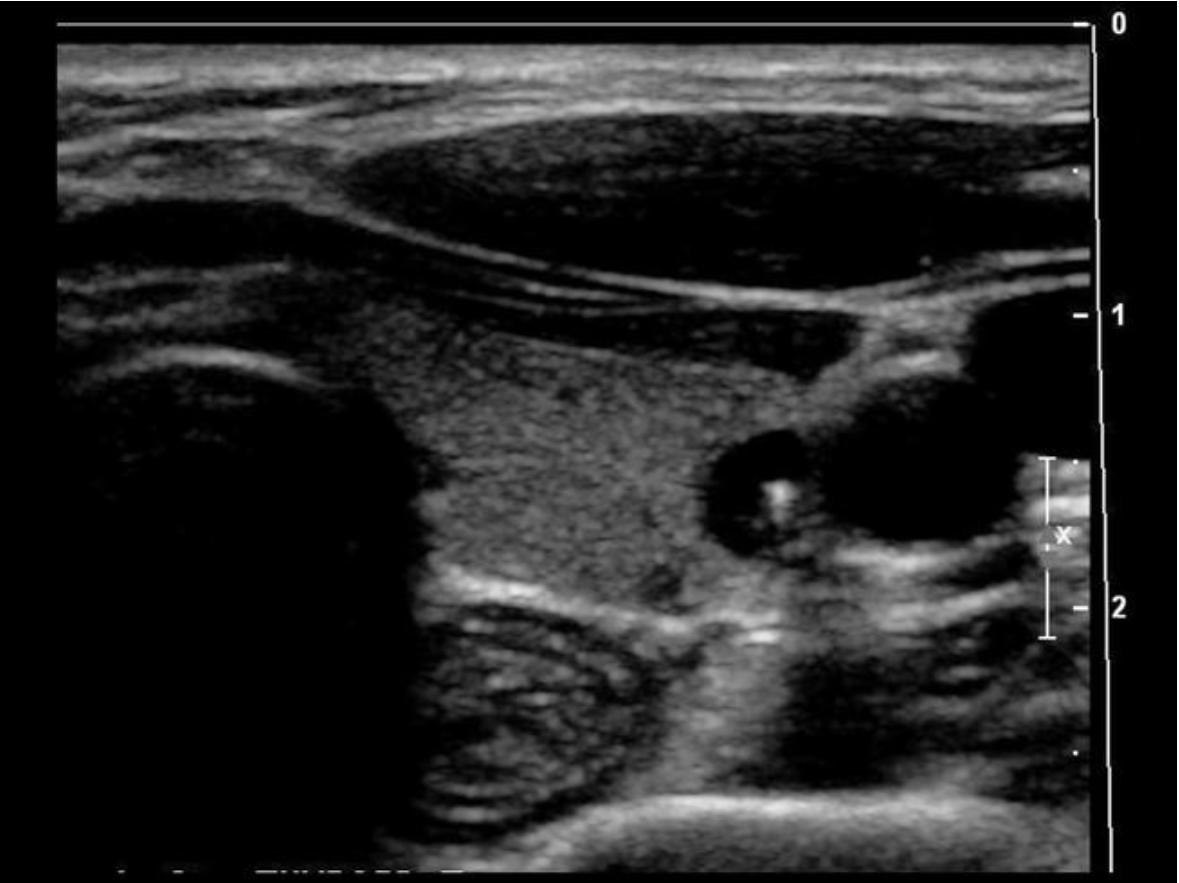

What is indicated by the yellow arrow?

C. esophagus

The arrow indicates the esophagus. Note the rings of tissue seen with normal Gl tract structures.

Which structure is visualized posterior and medial to the left lobe of the thyroid gland?

The strap muscles and the omohyoid muscle, one of the strap muscles, are anterior to the gland. The sternocleidomastoid muscles are anterior and lateral.

The longus colli muscles are on either side of the spine, posterior to the thyroid lobes. The esophagus is posterior and medial to the left thyroid lobe.